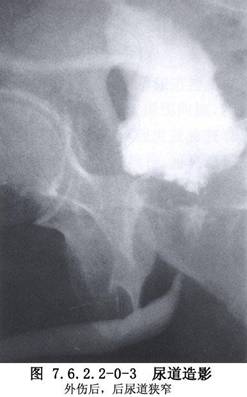

男性尿道狭窄是泌尿外科常见病,按其病因可分为先天性、炎症性和外伤性3类。先天性尿道狭窄较少见,如先天性尿道外口狭窄、尿道瓣膜、精阜肥大、尿道管腔缩窄等。炎症性尿道狭窄由特异性或非特异性尿道感染所致。特异性感染中,以淋病性尿道狭窄较常见;非特异性感染中,因反复包皮、阴茎头炎症所致的尿道外口及阴茎部尿道狭窄常见,因留置导尿管不当所致的炎症性尿道狭窄已引起广泛重视,这类狭窄多见于海绵体部尿道,范围较广;外伤性尿道狭窄(traumatic urethral stricture)是最常见的后天性尿道狭窄,狭窄部位依损伤部位而定,会阴跨骑伤所致者多在球部尿道。骨盆骨折所致者,位于膜部或前列腺尖端尿道,一般狭窄段不长,但瘢痕较坚硬(图7.6.2.2-0-1~7.6.2.2-0-3)。